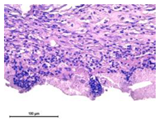

3.3.3. Morphological Study of Connective Tissue Capsules

Photographs of sections of the samples under study under various microscopy modes are shown in Table 8. Table 9 shows the distribution of the relative area of vessels (per 100 thousand µm2 of capsule area) for samples of magnesium calcium phosphate ceramics containing SPP, CA, and SPP_CA.

Sufficiently thick mature fibrous capsules with an increased content of vessels and pronounced inflammatory infiltration with a predominance of lymphocytes and neutrophils were mainly formed during implantation of samples of magnesium calcium phosphate ceramics of different compositions containing SPP. At the same time, the implant resorption was marginal with the penetration of single macrophages deep into the implant.

Only marginal resorption without penetration of macrophages deep into the implant was observed in the ceramic samples N0_CA and N0_SPP_CA. The introduction of single macrophages into the implant for composition N20, with a gradual increase for samples N40 and N60, was observed when newberyite appeared in the composition of the ceramics. Thinner capsules with less pronounced vascularization and inflammatory infiltration were formed during implantation of the magnesium calcium phosphate ceramic samples of different compositions with CA and SPP_CA. Compounds N40 and N60 actively germinated with fibroblasts.

The minimum relative area of vessels and capsule thickness is a characteristic of samples with CA, which confirms their biocompatibility. Biocompatibility increases in the range N0-N20-N40-N60 with all variants of setting inhibitors. Ceramics of the compositions N40_CA, N60_CA, N40_SPP_CA, and N60_SPP_CA have higher biocompatibility and resorption. The most mature thin fibrous capsule with moderate vascular content and weak inflammatory infiltration was observed. At the same time, intensive resorption of the implant by macrophages, giant multinucleated cells, and germination of ceramics by fibroblasts were observed.

Table 8. Section photos for the studied samples at different microscopy modes.

N0_LP0.7N20_LP0.7N40_LP0.7N60_LP0.7

SPPSLMCeramics 06 00011 i037Ceramics 06 00011 i038Ceramics 06 00011 i039Ceramics 06 00011 i040

PCMCeramics 06 00011 i041Ceramics 06 00011 i042Ceramics 06 00011 i043Ceramics 06 00011 i044

CASLMCeramics 06 00011 i045Ceramics 06 00011 i046Ceramics 06 00011 i047Ceramics 06 00011 i048

PCMCeramics 06 00011 i049Ceramics 06 00011 i050Ceramics 06 00011 i051Ceramics 06 00011 i052

CA_SPPSLMCeramics 06 00011 i053Ceramics 06 00011 i054Ceramics 06 00011 i055Ceramics 06 00011 i056

PCMCeramics 06 00011 i057Ceramics 06 00011 i058Ceramics 06 00011 i059Ceramics 06 00011 i060

SLM—standard light microscopy. PCM—phase-contrast microscopy. Hematoxylin-eosin, magnification 400×.

Table 9. The average thickness of fibrous capsules (µm) and the relative area of vessels per 100 thousand µm2 of capsule area. *—significant differences.

CompositionN0_LP0.7N20_LP0.7N40_LP0.7N60_LP0.7

SPPCASPP_CASPPCASPP_CASPPCASPP_CASPPCASPP_CA

Capsule thickness, µm602.6 ± 88.2108.0 * ± 6.9123 ± 15.9299.9 ± 15.1104.4 * ± 7.1116.7 ± 8.4531.1 ± 35.190.3 * ± 3.6104.7 ± 5.9213.9 ± 30.766.5 * ± 4.478.6 ± 2.9

p-level<0.0001<0.0001<0.00010.0002

Vessel area, µm2/100,000 µm2857.4 ± 303.54547.0 * ± 529.73973.2 ± 418.64130.0 ± 646.13525 ±309.23821 ±291.14394.0 ± 304.62825.0 * ± 445.93282.1 ± 234.85720.0 ± 19593259.0 ± 13452978.5 ± 245.3

p-level0.0040.4080.0080.306